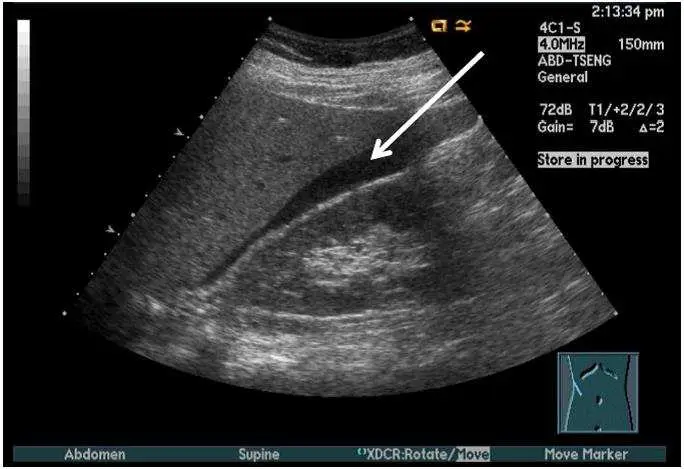

附圖所⽰ 為腹部超⾳波影像,箭號所指為下列何者?

影像為腹部超音波,探頭標示為 4C1-S(4.0 MHz 曲線探頭),掃描平面標示「Abdomen」,病人姿勢為仰臥(Supine)。畫面中可見:

- 前方:肝臟右葉(liver),呈均勻中等回音的實質結構。

- 後方:右腎(right kidney),可辨認其稍低回音的腎實質輪廓。

- 白色箭號所指:兩者之間出現一新月形(crescent-shaped)低回音至無回音(anechoic)條狀空間,位於肝臟下緣與腎臟前上方之間的界面。此即 Morison 隱窩,在此影像中其內有少量游離液體,呈現暗色帶狀。這是超音波上辨識 Morison 隱窩最典型的影像表現。